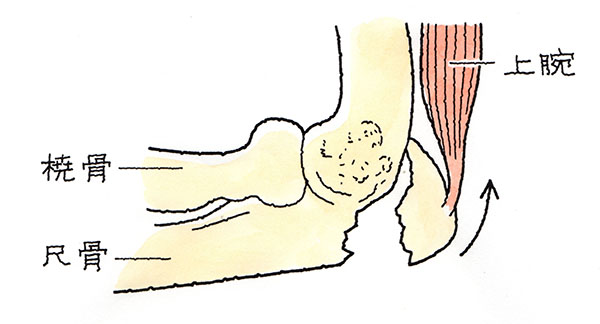

また、肘頭は、上腕三頭筋により上方へ引っ張られているので、これが骨折すると、骨がずれて転位が生じます。下のイラストのとおりです。

尺骨鉤状突起とは、尺骨と上腕骨の関節部分にある三角形に似た突起部分です。下のイラストの赤線のところです。

鉤状突起骨は鉤(かぎ)のように曲がって上腕骨を包んでおり、肘関節を前方に安定させるために重要な骨です。この部分の骨折が尺骨鉤状突起骨折です。